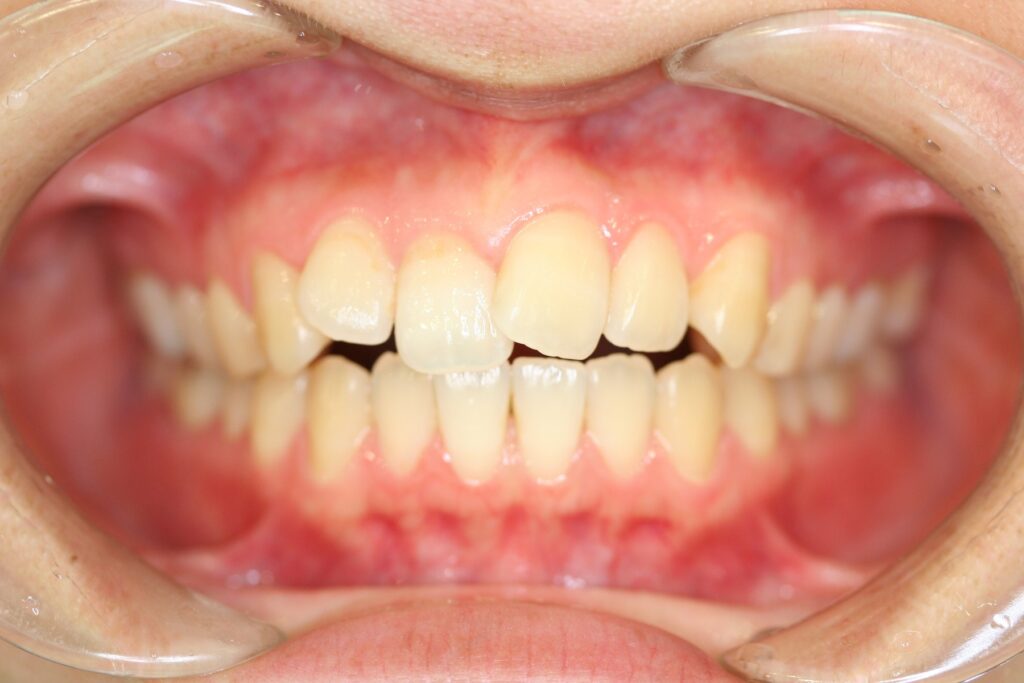

治療実績(症例) アライナー矯正 症例1 上顎前突症例 症例2 上下顎前突症例 症例3 叢生 症例4 開咬 症例5 開咬(外科的矯正治療) アライナー矯正 Post Share Hatena Line RSS feedly Pin it note 1.主訴2.診断名3.初診時年齢4.治療に用いた主な装置とオプション5.抜歯部位6.治療期間・通院回数7.総額と費用内訳総額相談検査・診断料調整料4,000円8.リスク・副作用 治療前 治療中 治療後